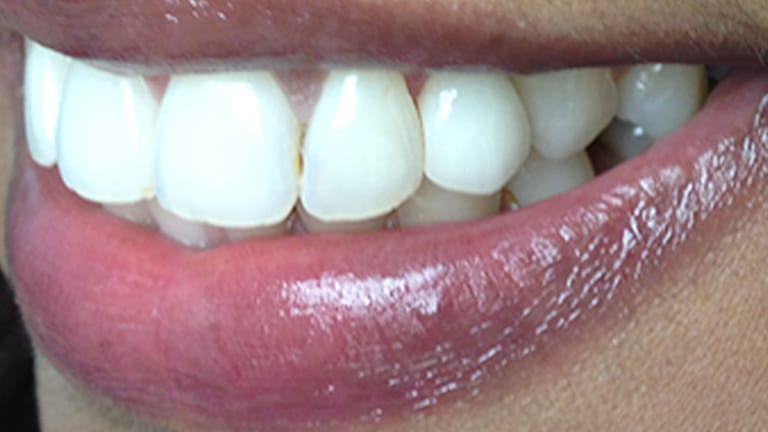

Below is a few examples of what DENTAL IMPLANTS can do for you and your smile!